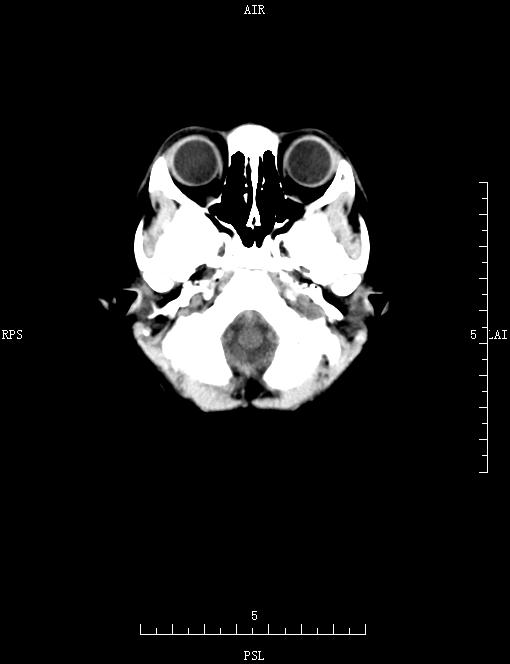

PED5344:头颅CT

男,5岁,头痛3天。

脑内未见明显异常。

两侧脑实质未见明显异常密度影,颅底及枕骨骨质呈磨玻璃样改变,部分骨质见透光区。考虑:颅骨骨纤维结构不良?